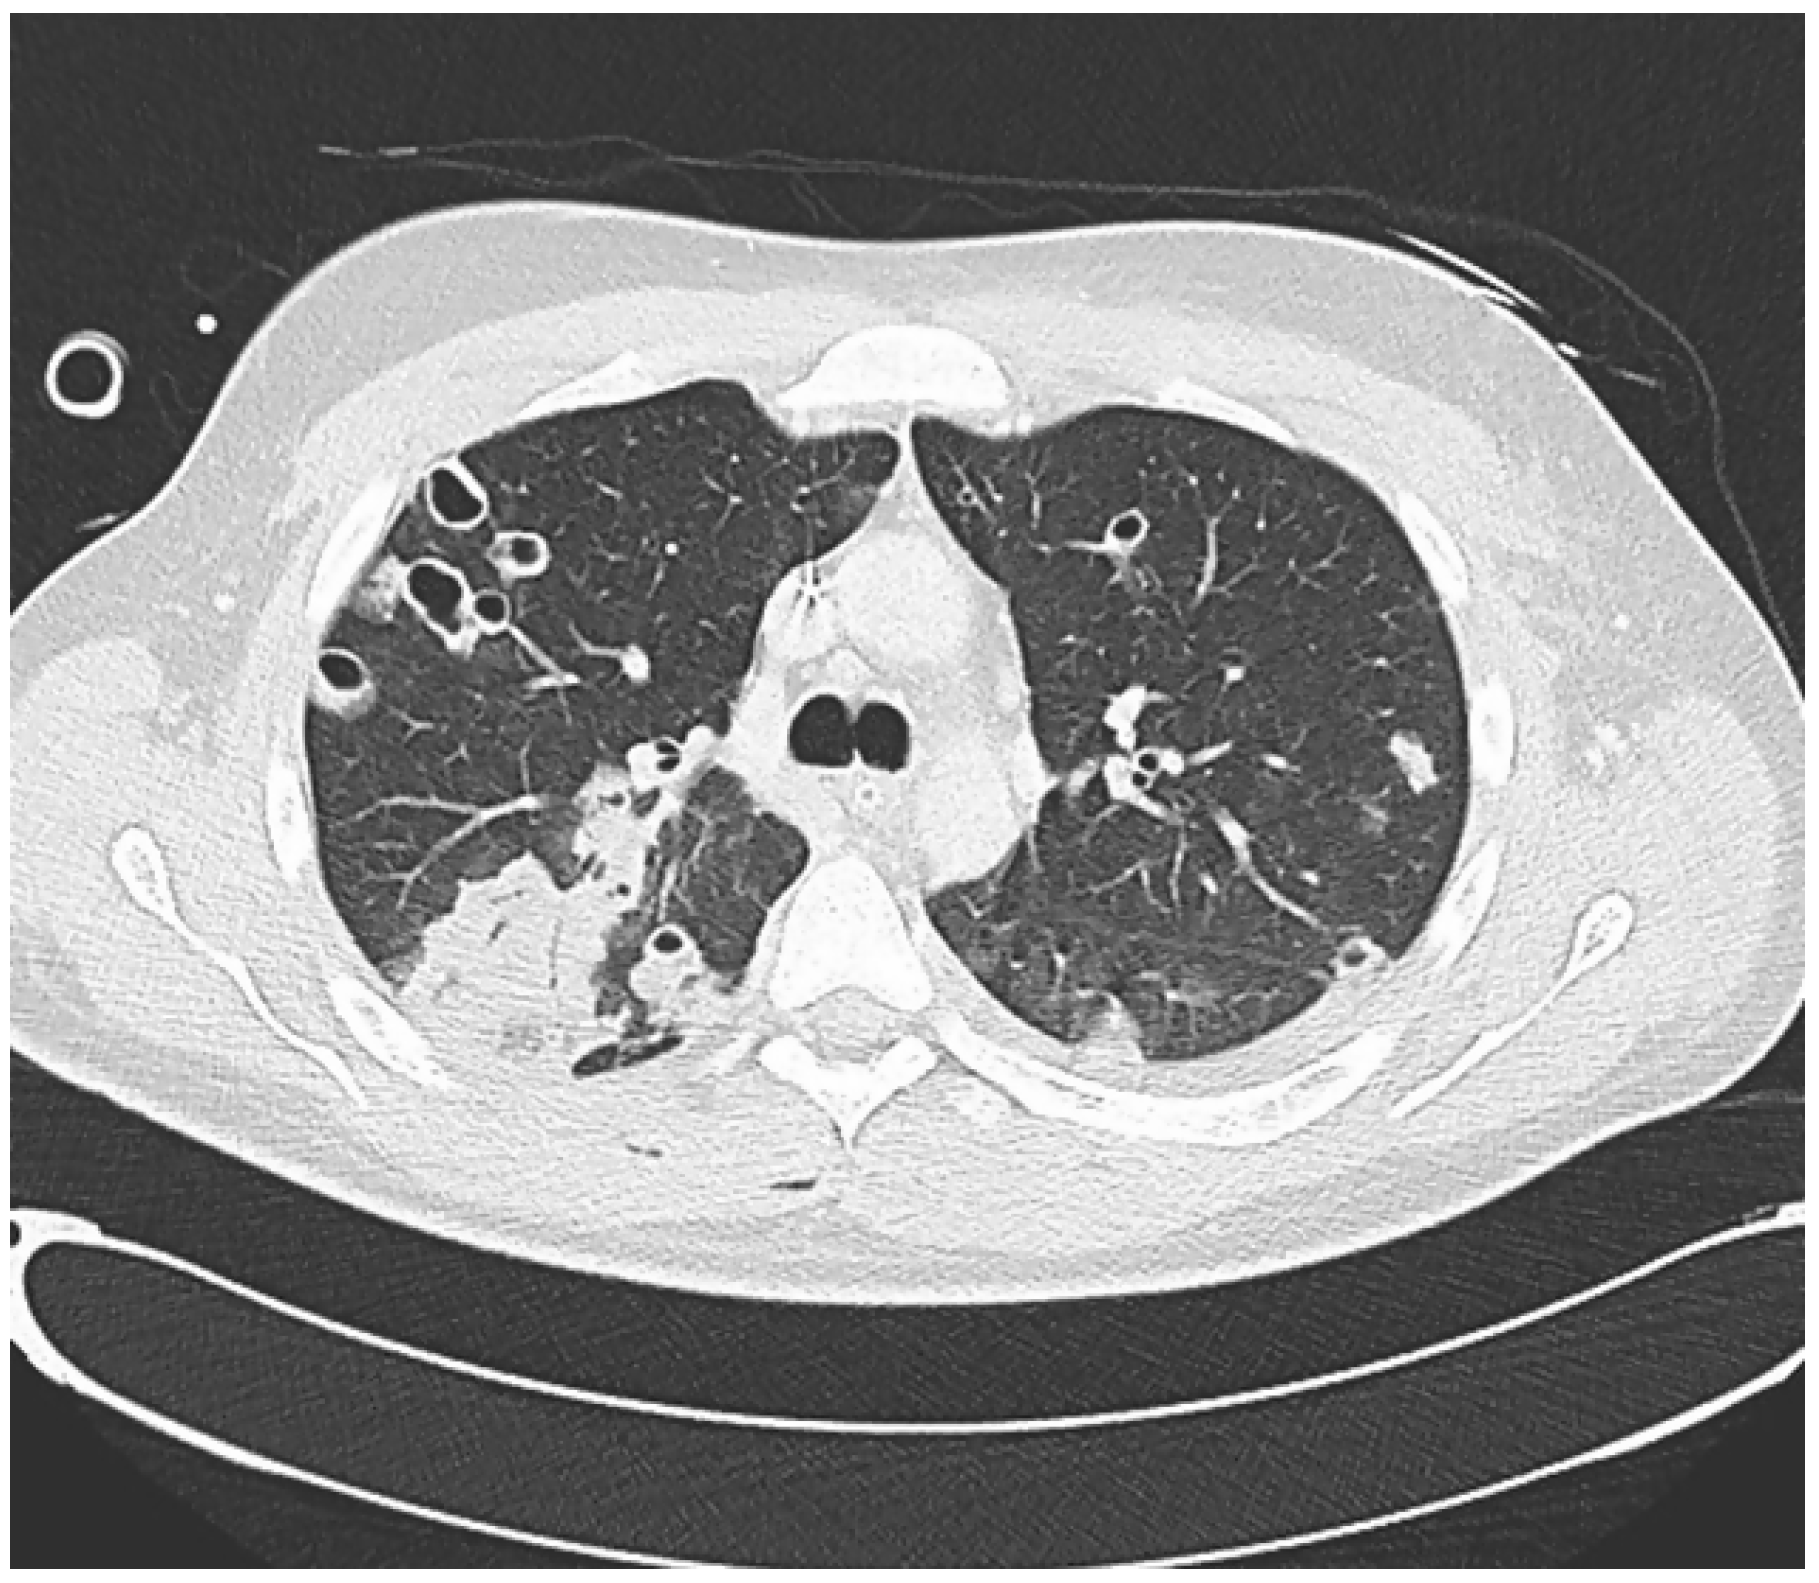

A CT scan of the thorax showed multiple pulmonary nodules some of which showed central cavitation distributed through the lung parenchyma corresponding to septic emboli with areas of ground-glass pattern (Figure 1).

Figure 1. Axial view of the chest CT scan showing multiple areas affected with pulmonary nodules, some of which show central cavitation and a consolidation image.